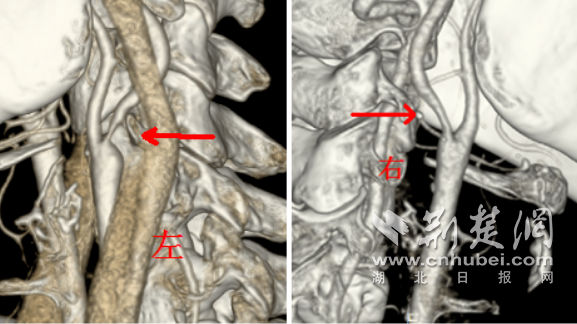

王女士的头颈部血管 CTA。 通讯员 供图

刘岳主任耐心细致地询问病史,并为其安排了针对性的检查。头颈部血管 CTA 结果显示:王女士的左侧颈动脉重度狭窄,右侧颈动脉也出现轻度狭窄。这意味着,患者大脑的供血通道已经严重受阻,如同水管被厚厚的污垢堵塞,随时有完全堵死的风险,即发生缺血性脑卒中。